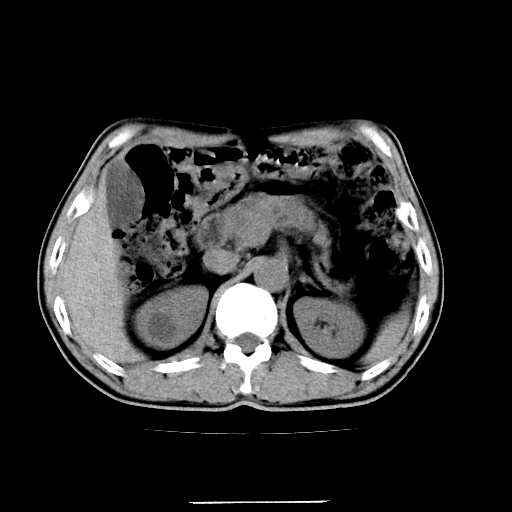

患者男,64岁,胃癌术后三个月,无明显不适。请讨论一下胰头前方小圆形低密度影为淋巴结还是肠管?

肠管吧.另外右肾见盂旁囊肿.

肠管.右肾见盂旁囊肿.

增强第6幅图上有气液平相通,是肠管,右肾低密度灶形态不规则似有壁结节,不除外转移.

是肠管,右肾低密度灶形态不规则、密度不均匀,不除外转移.

是肠管影。还有右侧肾盂旁囊肿。

是肠管影。还有右侧肾盂旁囊肿